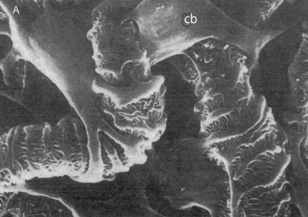

The epithelial lining of Bowman's capsule consists of a single layer of cells (podocytes), which rest on the basement membrane. The podocytes have large extensions or trabeculae, which extend out from the cell body and are embedded in the basement membrane surrounding a capillary. Small processes called pedicels extend out from the trabeculae and interdigitate extensively with the pedicels of adjacent trabeculae. This leads to the formation of slit pores, which control the movement of substances through the final layer of the filter. The podocytes have a well-developed Golgi apparatus, used to produce and maintain the glomerular basement membrane. Podocytes can also be involved in phagocytosis of macromolecules (Figs 2.1 and 2.2).

image image

Fig. 2.2 Electron micrographs showing the arrangement of podocytes and glomerular capillaries as seen from Bowman's capsule. (A) Processes of podocytes run from the cell body (cb) towards the capillaries where they ultimately split into foot processes (pedicels). (B) Inner surface of a glomerular capillary.

(From Koeppen BM, Stanton B, 1996. Renal physiology, 2nd edn. Mosby Year Book.)